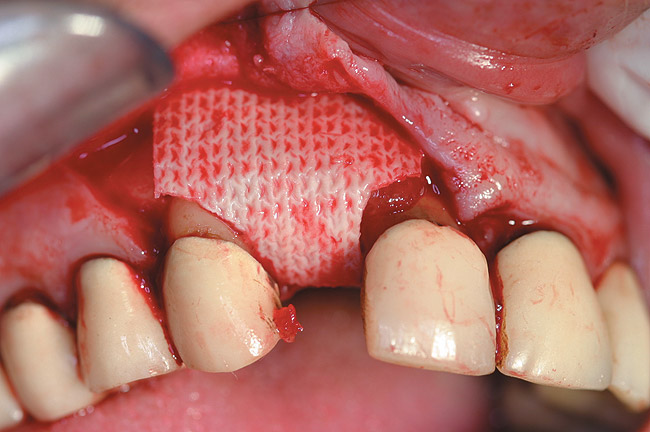

RegenerOss™ Allograft Putty (BIOMET 3i™, www.biomet3i.com) was molded to form the contours of the desired future ridge (Figure 3), and a 20-mm x 30-mm Ossix® Plus membrane (Colbar LifeScience, Ltd, Herzlya, Israel) was trimmed and adapted to cover the graft material (Figure 4). Periosteal relaxing incisions were made, and passive primary closure was obtained.

Figure 4  The Ossix Plus resorbable collagen membrane in place.

Figure 4